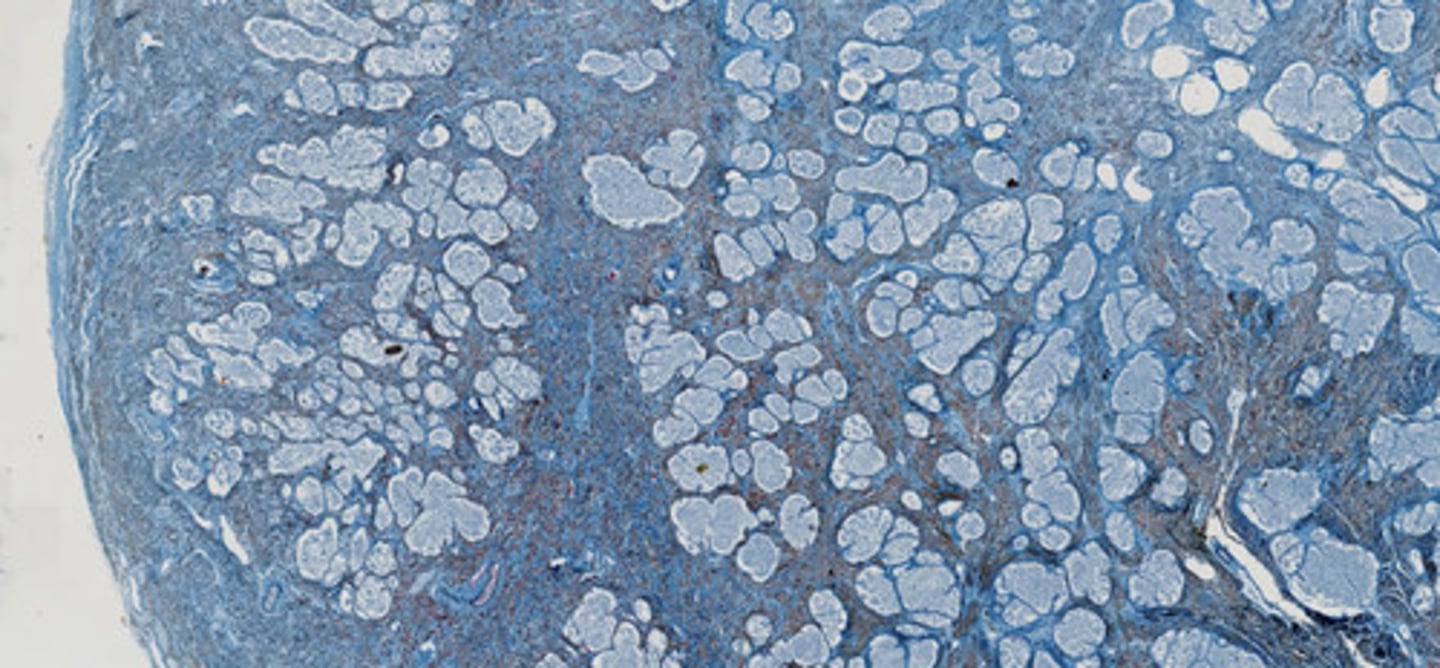

Nerka nastrzyknięta - obrazowanie naczyń (masa iniekcyjna z błękitem metylu)